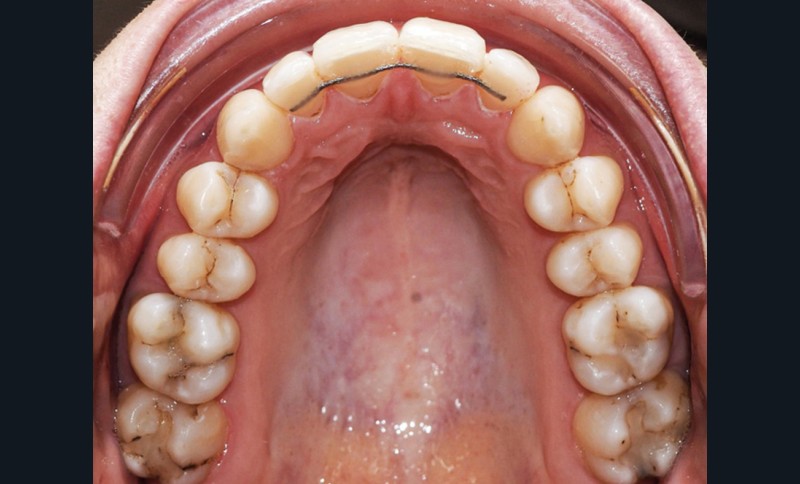

Examen endo-buccal (fig. 2a-e)

L’arcade maxillaire est parabolique, la 12 présente une légère mésio-rotation. L’arcade mandibulaire est également parabolique avec un encombrement antérieur estimé à 6 mm. On note une dyschromie de la 31, dont le test de vitalité est négatif. Le parodonte est fin.

Les incisives maxillaires sont de forme triangulaire [1] et l’indice de Bolton est de 97 % qui traduit la présence d’une DDD par excès mandibulaire.

Le choix final s’est donc porté sur l’extraction de la 31 avec stripping maxillaire. Ce stripping avait deux objectifs : corriger la DDD créée par l’extraction de 31 (indice de Bolton de 90,8 % post extraction, soit une DDD par excès maxillaire) et éviter l’apparition de triangles noirs entre les incisives maxillaires liée à leur forme triangulaire [1]. Le set-up réalisé en début de traitement lingual est un avantage car il permet de prévisualiser la correction de la DDD créée et la quantité de stripping nécessaire.

Du stripping a été effectué de 13 à 23, à l’aide de fines fraises diamantées.

Après dépose du multi-attaches, des contentions collées ont été posées de 12 à 22 et de 33 à 43 et des gouttières thermoformées ont été ajoutées en complément en cas de problème avec les fils de contention.